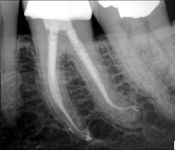

Pictured: Root Fractures/Splinting of Teeth and 1 Year Recall with Complete Root Formation

Parent of our 7-year-old patient was distraught by an injury that indicated horizontal root fractures in tooth #8 and tooth #9. Treatment involved splinting of teeth. After 1 year recall , the patient successfully had complete root formation.